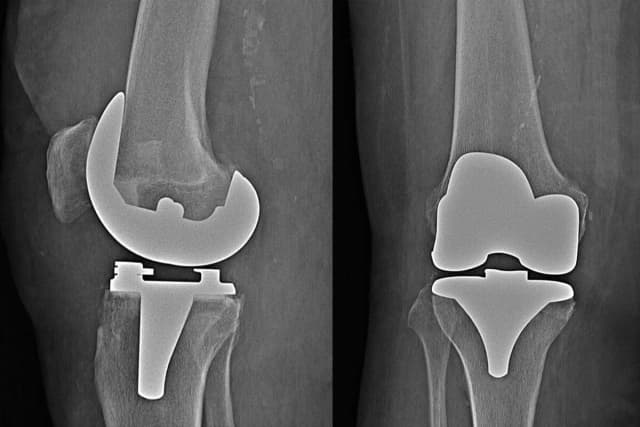

Sprawdź, jakie badania przed operacją endoprotezy są kluczowe dla sukcesu zabiegu i jak mogą wpłynąć na Twoje zdrowie oraz bezpieczeństwo.